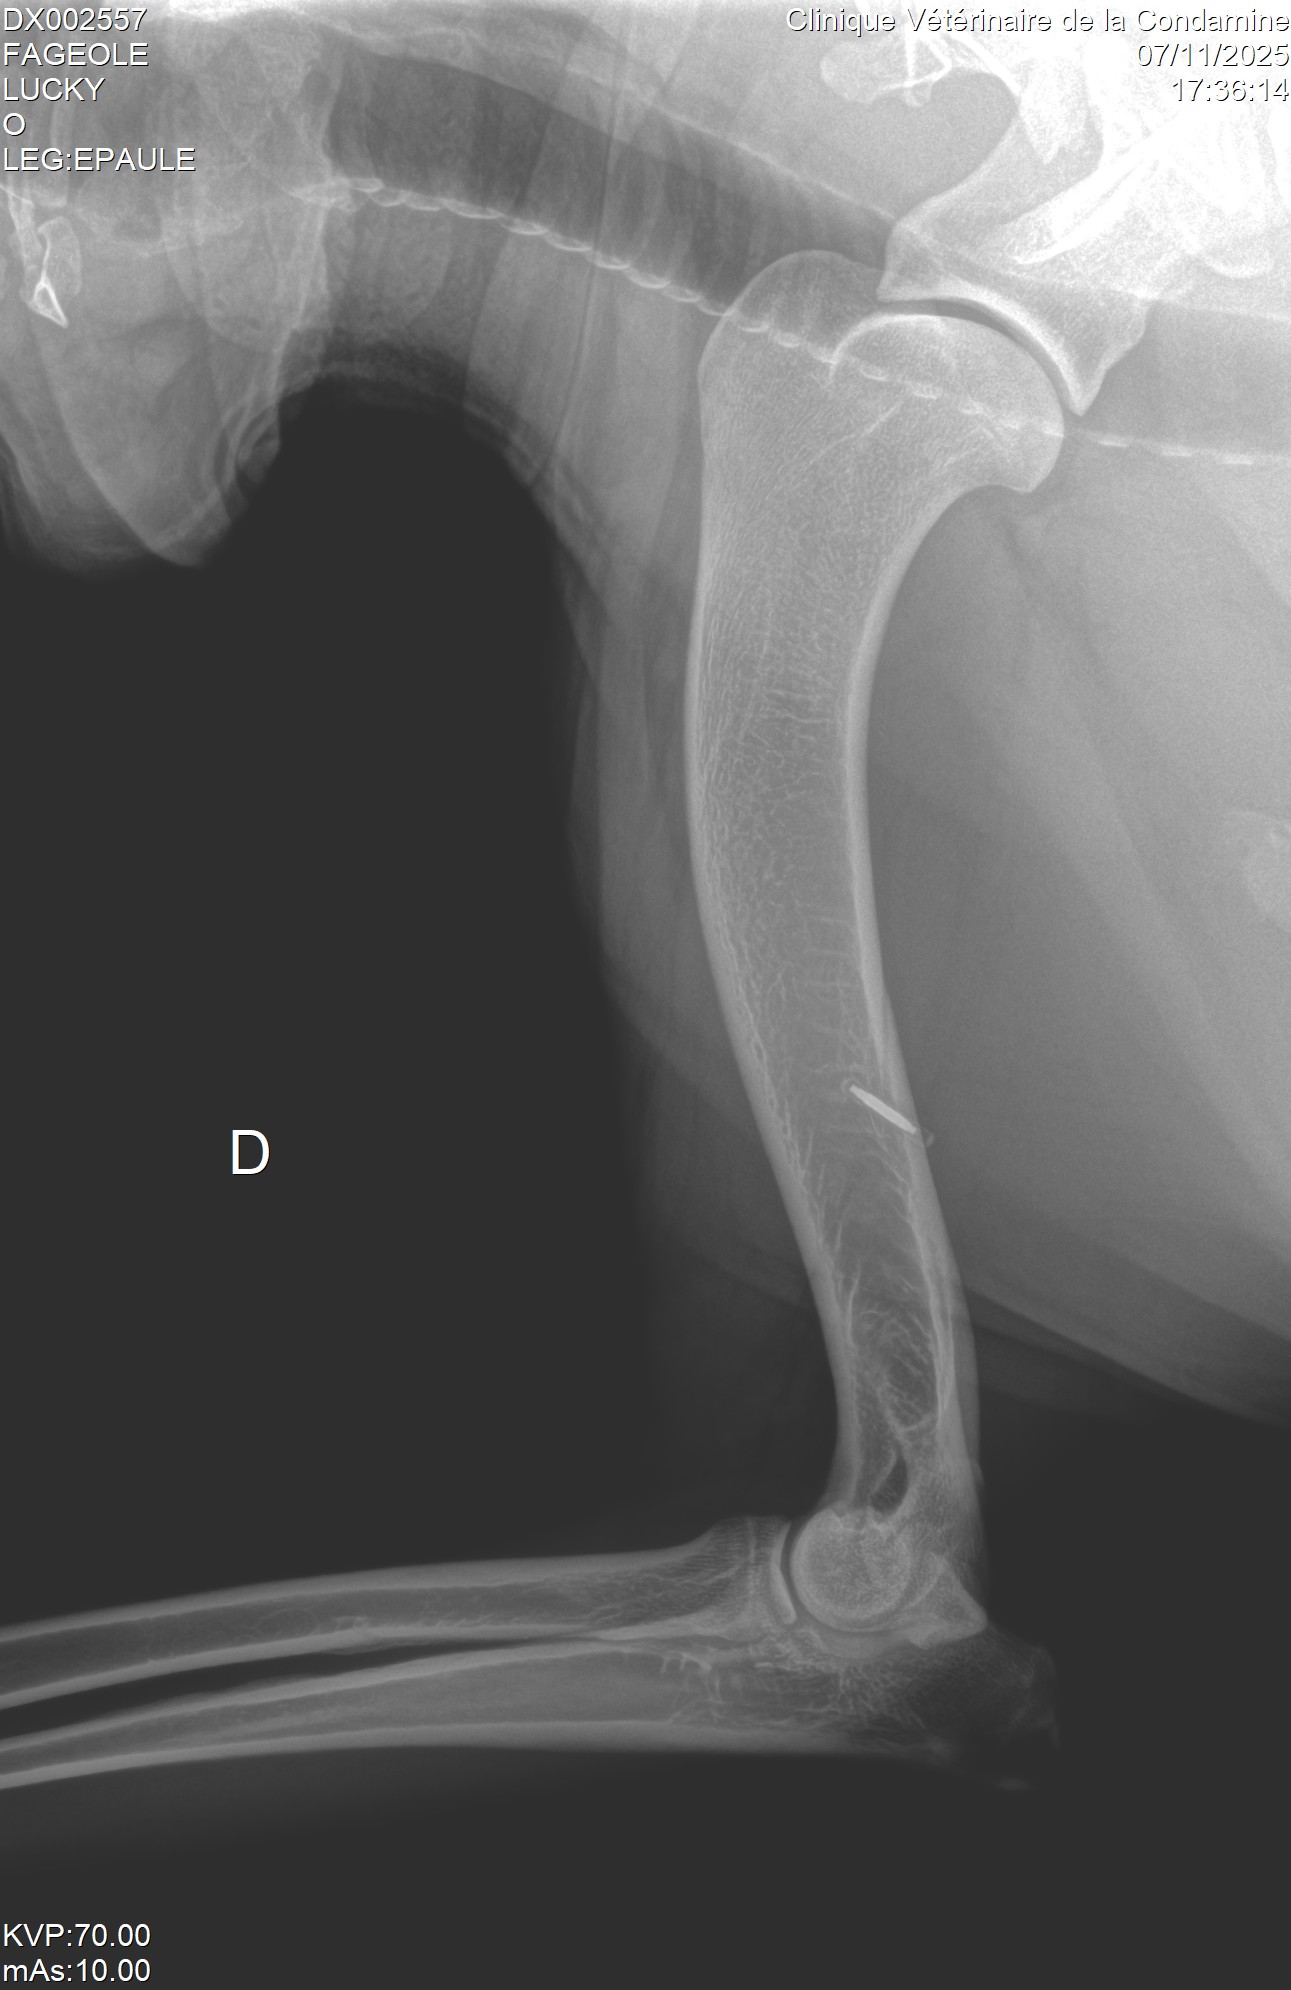

Aide interpretation radio

2025-11-07 14:46:30

放射学